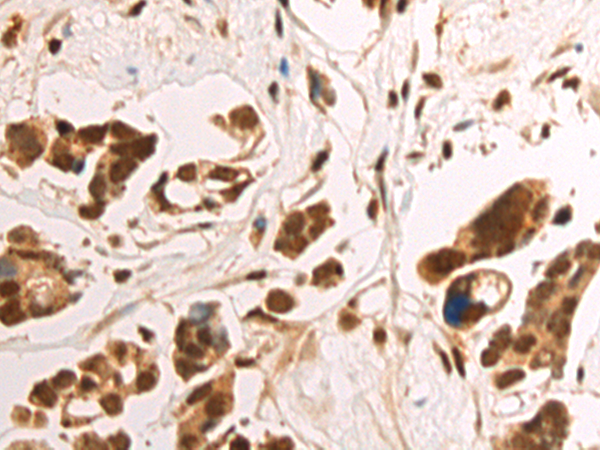

分类: 科研抗体货号: P09736别名: RVB1; TIH1; ECP54; TIP49; ECP-54; INO80H; NMP238; PONTIN; TIP49A; NMP 238; Pontin52应用: WB,IHC反应种属: Human, Mouse, Rat